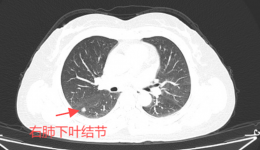

近日,广西壮族自治区桂东人民医院心胸外科团队自主完成一项高难度的手术—保留自主呼吸非插管麻醉下的微创肺癌根治手术。此次手术不仅体现了桂东人民医院心胸外科团队的高超技艺和丰富经验,也展示了医院在胸外科精准治疗领域的不断探索和创新。54...